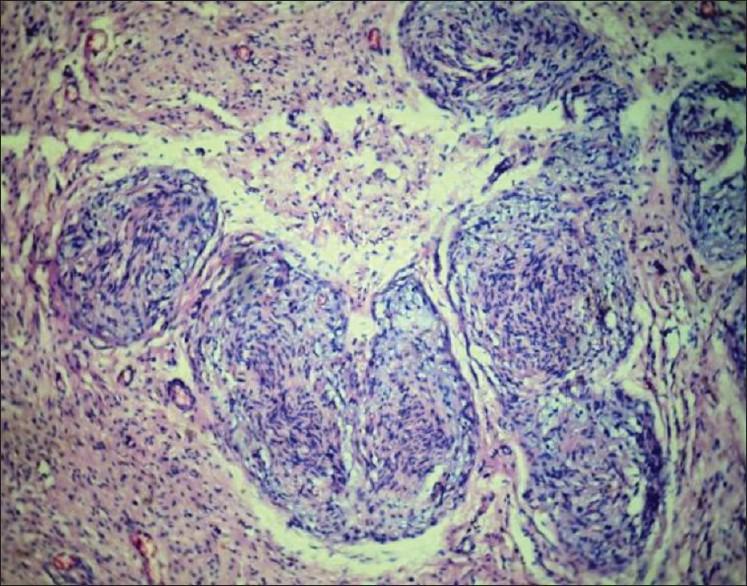

A 70-year-old female patient presented with proptosis of right eye for the past 15 days and defective vision in both eyes since birth. She was found to have eccentric painful proptosis of right eye along with features of oculocutaneous albinism. Eccentric proptosis was due to an orbital mass which proved to be a plexiform neurofibroma by histopathological examination. The case is presented for its rarity, as an isolated orbital plexiform neurofibroma without the systemic features of neurofibromatosis is rare and its coincidental presentation with oculocutaneous albinism is yet rare and has not been reported so far.

一名70岁女性患者,右眼突出15天,自出生起双眼视力不佳。检查发现患者右眼有偏心性疼痛性眼球突出,并伴有眼皮肤白化病特征。偏心性眼球突出是由眼眶肿块引起的,经组织病理学检查证实为丛状神经纤维瘤。该病例因其罕见性而被报道,孤立性眼眶丛状神经纤维瘤而无神经纤维瘤病的全身特征较为罕见,其与眼皮肤白化病同时出现则更为罕见,迄今为止尚未见报道。